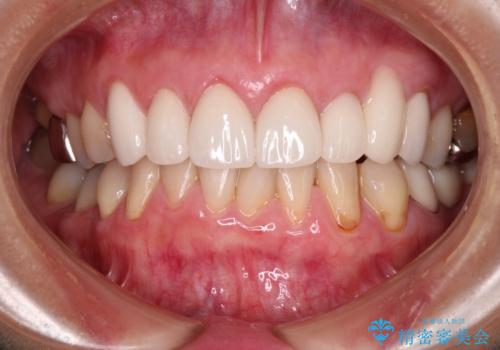

歯肉移植による根面被覆の結果、しみる症状は一切なくなりました。

歯肉の厚みが増したため、歯肉退縮のリスクが軽減されましたが、定期的に症状が再発していない確認していくことになります。